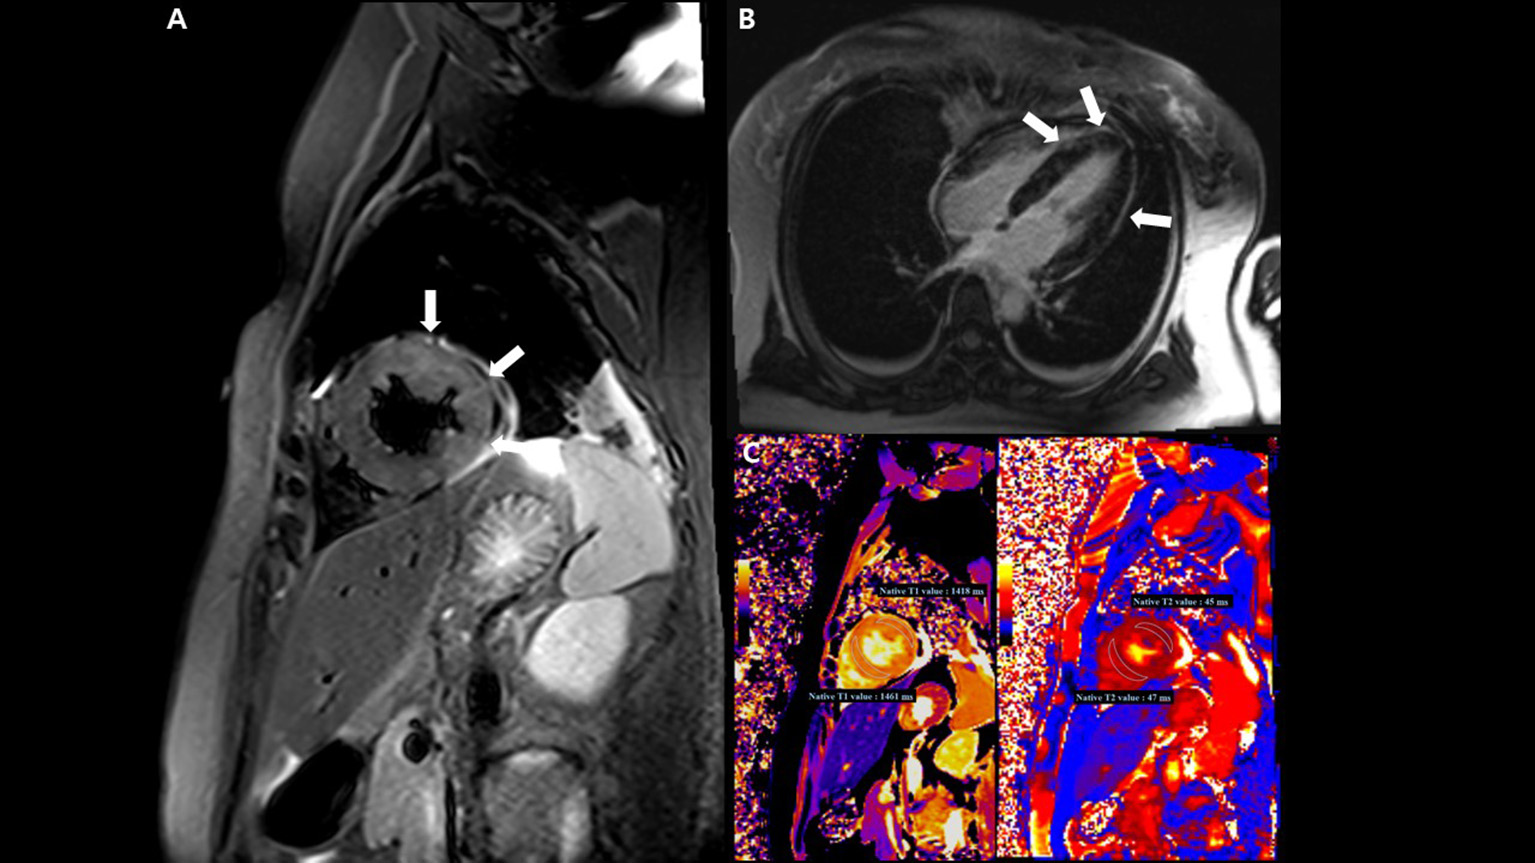

On the tenth day, cardiac magnetic resonance imaging was performed, which showed multifocal lesions with high signal intensity in T2 weighted images (Figure 4A) and a positive late gadolinium enhancement (Figure 4B) which implies myocardial edema and necrosis, respectively. In addition, both T1 and T2 relaxation times at the LV wall were also increased (Figure 4C).

Figure 4

Cardiac magnetic resonance imaging (MRI) findings. (A) T2-weighted short TI inversion recovery MRI at 3T in a short-axis view shows multifocal high signal intensities at the mid anterior and lateral wall (arrow) indicating myocardial edema. (B) Late gadolinium enhancement imaging in a four-chamber view displays multifocal mid wall enhancement (arrow) indicating inflammatory myocardial necrosis. (C) T1 mapping and T2 mapping in a short-axis view show elevated T1 and T2 relaxation times at the mid ventricular level, indicating an acute myocardial injury (regional T1 relaxation time-1,418 ms at the anterolateral wall and 1,461 ms at the septal wall, regional T2 relaxation time-45 ms at the anterolateral wall and 47 ms at the septal wall; institution-specific cutoff values for acute myocarditis- T1 global: ≥1,230 ms and T2 global: ≥36 ms).